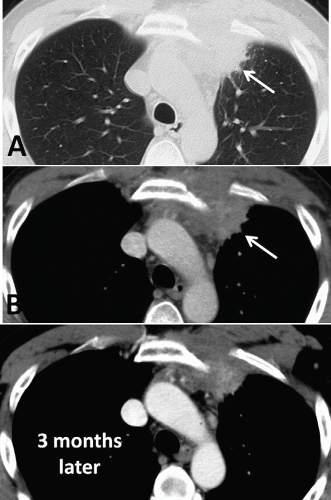

CFig.1.6 Computedtomography(CT)scanofapatientwithanteriorchestwallpain.CTscanningof anterioruppermediastinalmassafteriodinatedcontrastadministration.Lungwindow(A). Mediastinumwindow(B)showsinhomogeneouscontrastenhancementofthemass.Enhanced multidetectorCTfollow-upafter3months(C)showsdecreaseinvolumeofmediastinalmass. (FromDeFilippoM,AlbiniA,CastaldiV,etal.MRIfindingsofTietze ’ssyndromemimickingmediastinalmalignancyonMDCT. EurJRadiolExtra .2008;65(1):33 35[Fig.1].ISSN1571-4675, https:// doi.org/10.1016/j.ejrex.2007.10.006, http://www.sciencedirect.com/science/article/pii/S1571467 507000892.)

Plainradiographsareindicatedforall patientswhopresentwithpainthatis thoughttobeemanatingfromthecostosternaljointstoruleoutoccultbony disorders,includingtumor( Fig.1.5 ).Iftraumaispresent,radionuclidebone scanningmaybeusefultoexcludeoccultfracturesoftheribsorsternum. Basedonthepatient ’ sclinicalpresentation,addi tionaltestingmaybeindicated,includingacompletebloodcount,pr ostate-specificantigenlevel,erythrocytesedimentationrate,andantin uclearantibodytesting.Laboratory evaluationforcollagenvasculardiseaseisindicatedinpatientssufferingfrom costosternaljointpainifotherjoin tsareinvolved.Computedtomography

(CT)scanning,magneticresonanceimag ing(MRI),andultrasoundimagingof thejointsareindicatedifjointinstabilityoroccultmassissuspected,ortoelucidatethecauseofthepainfurther( Figs.1.6,1.7 ,and 1.8 ).Injectionofthe costosternaljointcanserveasbothadi agnosticandatherapeuticmaneuver ( Figs.1.9 and 1.10 ).